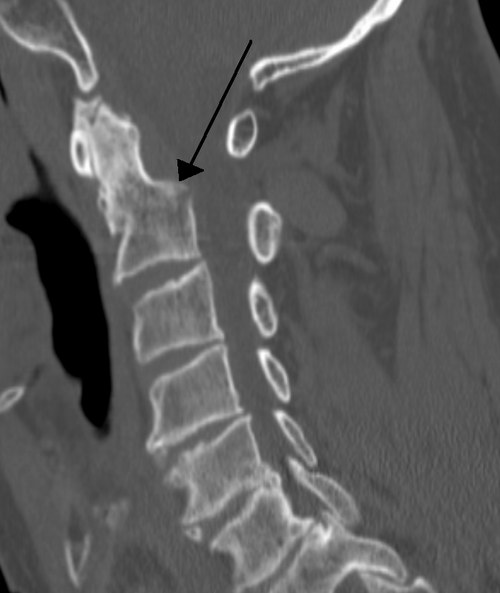

Cervical fracture

James Heilman, MD · CC BY-SA 3.0 · source

Cervical fracture is an acute break in one or more of the vertebrae of the cervical spine located in the neck. It commonly presents after high-energy trauma and may be associated with spinal cord compromise, requiring rapid evaluation by Trauma center teams, Emergency medicine clinicians, and specialists in Neurosurgery and Orthopaedics. Timely imaging, immobilization, and multidisciplinary management influence outcomes and long-term function.

Fractures are classified by pattern and stability, referencing systems used by entities like AO Foundation, Denis classification proponents, and schemes cited in guidelines from National Institute for Health and Care Excellence. Examples include odontoid (dens) fractures frequently discussed in literature from Mayo Clinic, hangman fractures involving C2 studied at Cleveland Clinic, and burst fractures evaluated by investigators at Johns Hopkins University. Subtypes such as type I, II, and III odontoid fractures are described in textbooks used at Yale School of Medicine and Stanford University School of Medicine. Stability assessment aligns with paradigms from American Association of Neurological Surgeons and Congress of Neurological Surgeons recommendations.

Initial assessment follows trauma algorithms promulgated by Advanced Trauma Life Support and involves cervical immobilization policies from American College of Surgeons. Imaging begins with high-resolution Computed tomography scans as performed at centers like Karolinska Institutet and may be supplemented by Magnetic resonance imaging to evaluate the spinal cord and ligaments as in studies by Toronto Western Hospital. Plain radiographs remain useful in resource-limited settings referenced by Médecins Sans Frontières and World Health Organization advisories. Neurological examination may use scales developed by Frankel grading system proponents and the American Spinal Injury Association (ASIA) impairment scale applied in multicenter trials coordinated through institutions such as Sydney Neurotrauma Centre.